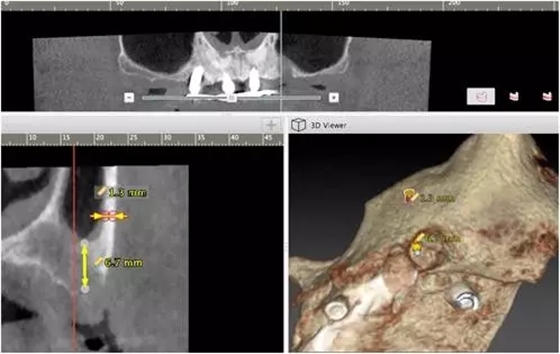

10個月后出現(xiàn)左上頜咬合痛,X線檢查發(fā)現(xiàn)上頜左側(cè)前磨牙區(qū)傾斜種植體周圍低密度影,臨床檢查種植體松動,其余種植體骨結(jié)合良好,遂拔除該種植體(圖3-4)。愈合3個月,CBCT片顯示:25區(qū)種植窩空虛(圖5),愈合不佳,26區(qū)竇底剩余骨高度不足2mm(圖6),其余種植體骨愈合良好,15區(qū)傾斜種植體邊緣骨疑似吸收至第三螺紋(結(jié)合全景片)?;颊咭蠊潭ㄐ迯?fù)。

1、在25區(qū)補種1顆傾斜種植體,恢復(fù)ALL-on-4修復(fù)方案。造成之前種植體失敗的原因與其受力有關(guān),可能來自于修復(fù)體的咬合設(shè)計,也可能源于上、下頜種植體數(shù)量上的差異(通常上頜種植體數(shù)量應(yīng)多于下頜)。另外,放射學(xué)檢查顯示,15區(qū)種植體邊緣骨吸收較明顯,也提示存在支撐力不足的問題。后來追問病史,該患者修復(fù)后有夜磨牙情況,這進一步證實了上述判斷。鑒于此,這個方案暫不做考慮。2、增加上頜種植體數(shù)量,分別與16、25、26植入3顆,行6顆種植體支撐的常規(guī)種植固定義齒修復(fù)(圖7)。16、25、26區(qū)剩余骨高度嚴(yán)重不足是該方案的不利方面,存在因需要上頜竇底提升手術(shù)所帶來的相應(yīng)手術(shù)風(fēng)險。但是,上頜竇底提升術(shù)是一個成熟、可靠的技術(shù)方法,經(jīng)過與患者充分溝通,最終選擇了這一方案。

1、開窗法雙側(cè)上頜竇底提升術(shù),聯(lián)合25區(qū)植骨術(shù);2、6個月后延期種植,分別與16、25、26植入3顆種植體(如圖7所示);為什么選擇開窗法上頜竇底提升延期種植手術(shù)方案?上頜竇底提升同期種植的標(biāo)準(zhǔn)是植入種植體能夠獲得初期穩(wěn)定性,竇底植骨材料不具有增加種植體穩(wěn)定性的作用,共識性意見認(rèn)為剩余骨高度一般應(yīng)大于4-5mm。開窗法是骨高度嚴(yán)重不足進行上頜竇底提升的有效和可靠術(shù)式。當(dāng)然,國際上也有關(guān)于采用沖壓法提升剩余骨高度僅有1-2mm上頜竇底的成功病例報道,但是目前尚缺乏大樣本、多中心重復(fù)性的臨床研究證明,還沒有得到廣泛的國際共識,不易作為常規(guī)術(shù)式,有待未來進一步的研究。為什么有越來越多種植體掉入上頜竇內(nèi)的病例發(fā)生?這是一個應(yīng)該盡量杜絕的并發(fā)癥,即使臨床發(fā)生率并不高。盲目擴大同期種植適應(yīng)證、種植體無初期穩(wěn)定性是其主要原因。北一種植老師總結(jié):無論種植技術(shù)如何發(fā)展,如何進步。作為一名種植醫(yī)生掌握上頜竇外提升手術(shù)及內(nèi)提升手術(shù)是一項基本功。 因此需要所有醫(yī)生熟練掌握,應(yīng)對各種并發(fā)癥大有幫助。